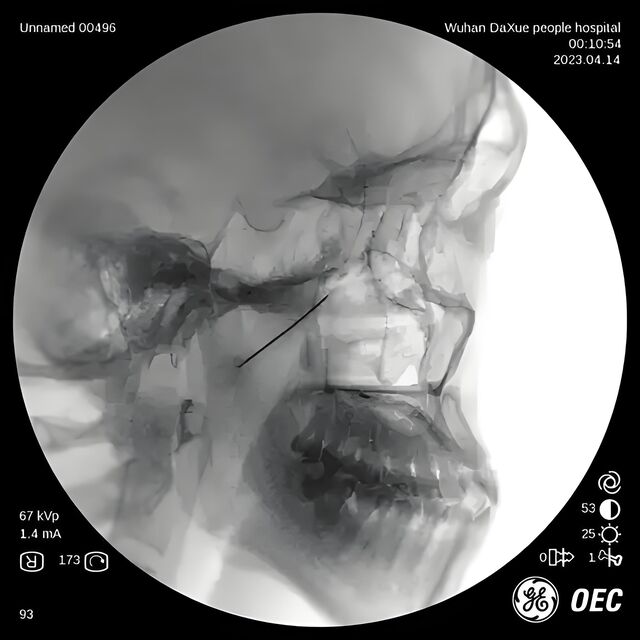

针具到位:

蝶腭神经节针刺

治疗过敏性鼻炎